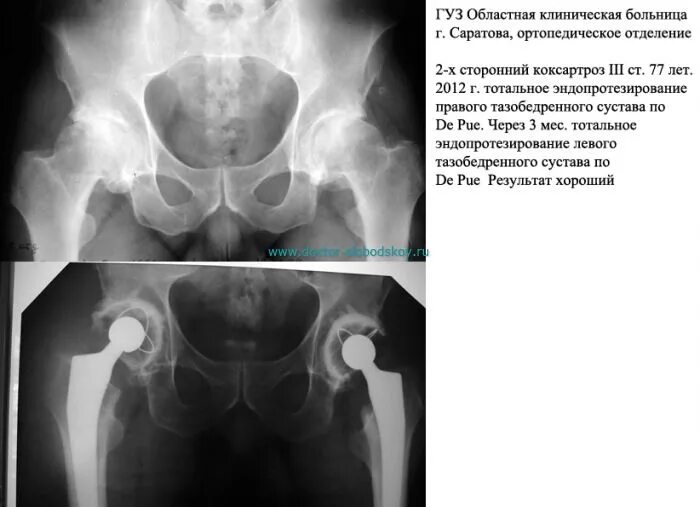

Коксартроз тазобедренного 3 степени операция